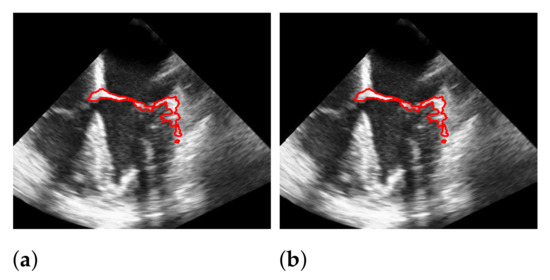

5.3. Windowing

5.4. Segmentation with Windowing